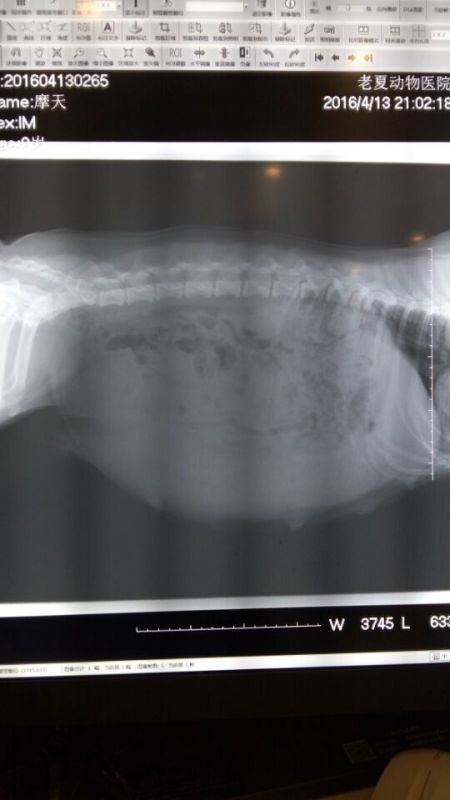

美国超级登陆冠军,中国登陆冠军“克鲁尼”直子中国登陆冠军“旺财”搭配日本登陆冠军“JACKY”直女“Magic day”,现已带胎,预产期本月28日,本胎预计为双色奶油脸,现首二选母,选公,二选公接受预定,欢迎咨询!